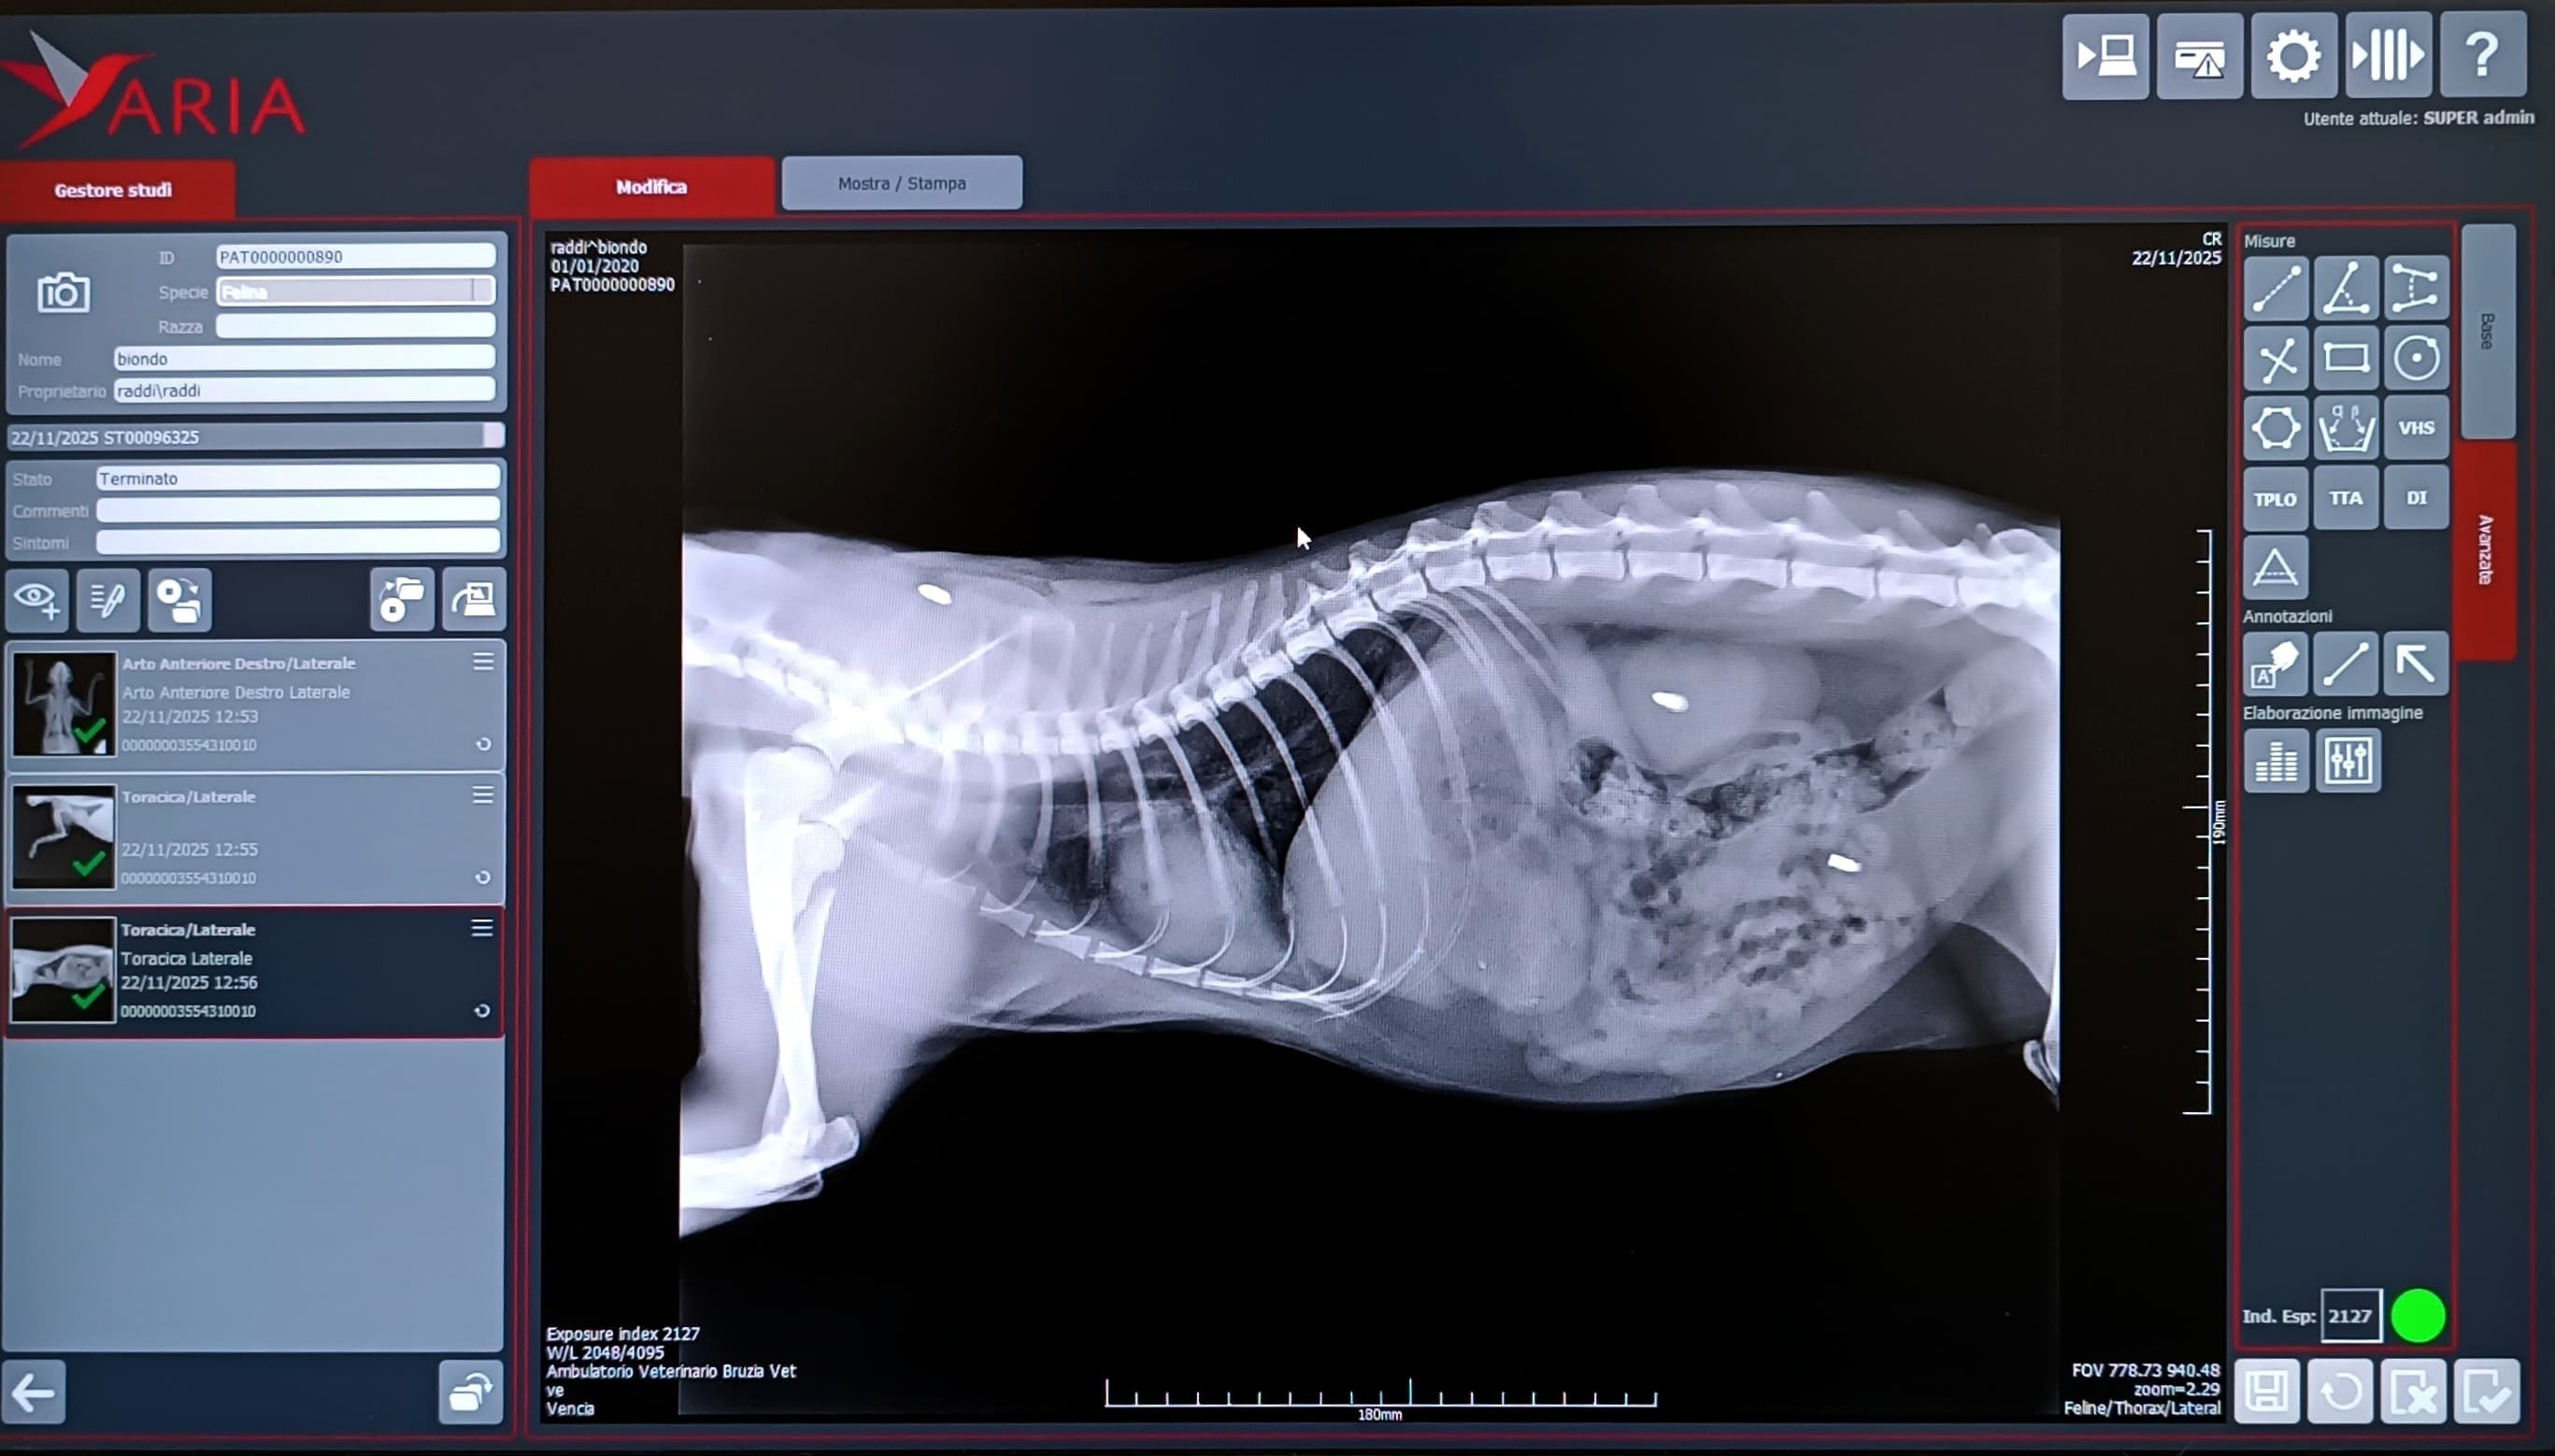

Un ragazzo di 25 anni, senza grandi mezzi ma con un cuore enorme, ha ascoltato i miei miagolii e non ha voltato lo sguardo. Nonostante la paura e la mia sofferenza, è riuscito a prendermi tra le sue braccia e portarmi dal veterinario. Le radiografie hanno mostrato la verità: una grave frattura alla zampa anteriore, tre proiettili ancora nel corpo e una vita segnata da violenze subite.